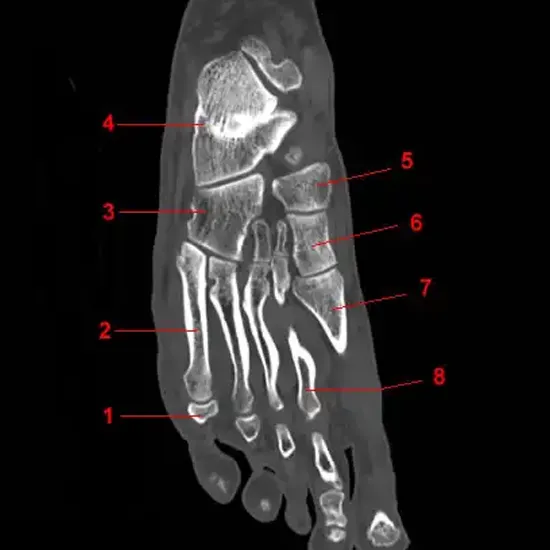

CECT Left Foot is an imaging scan in which contrast is injected to visualize the bony details of the left foot and its soft tissue injury.

• To detect fracture and dislocation in the left foot

• To detect soft tissue injury of left foot

• Inflammatory arthritis of the left foot

• Infection

• The trauma of the left  foot